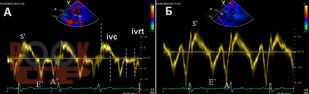

В книге освещена роль негативного влияния нарушения внутрижелудочкового проведения на усугубление диастолической дисфункции, апикальной ротации, скручивание левого желудочка. Особое внимание уделено деформации левого предсердия при стресс-эхокардиографии с физической нагрузкой у лиц с сохраненной фракцией выброса левого желудочка. Показана тесная связь деформации левого предсердия с апикальной ротацией левого желудочка. Представлены данные о деформации правого желудочка в покое и при физической нагрузке у пациентов с блокадой правой ножки пучка Гиса.